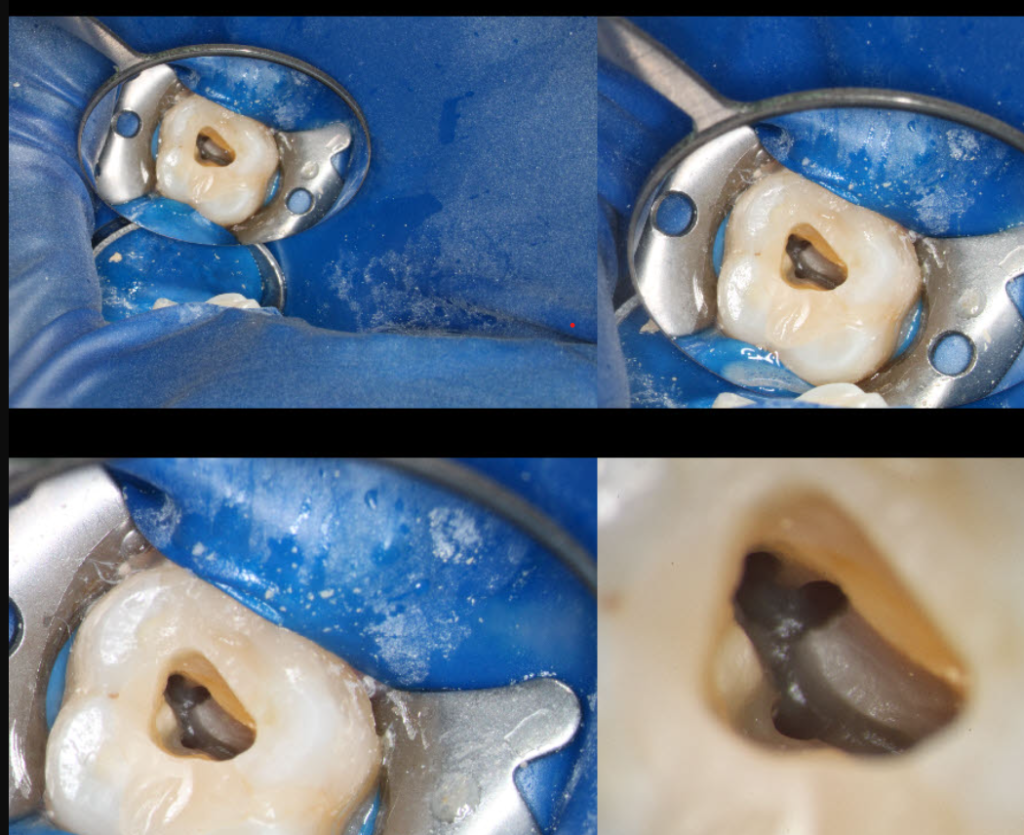

Снимка, илюстрираща увеличението на микроскопа.